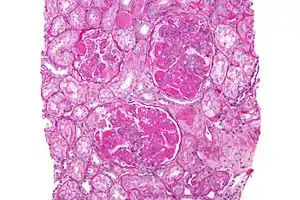

In DPGN Most of the glomeruli show endothelial and mesangial proliferation, affecting the entire glomerulus, leading to diffuse hypercellularity of the glomeruli, producing in some cases epithelial crescents that fill Bowman's space. When extensive, immune complexes create an overall thickening of the capillary wall, resembling rigid "wire loops" on routine light microscopy. Immune complexes can be visualized by staining with fluorescent antibodies directed against immunoglobulins or complement, resulting in a granular fluorescent staining pattern. Electron microscopy reveals electron-dense subendothelial immune complexes (between endothelium and basement membrane). In due course, glomerular injury in DPGN gives rise to scarring (glomerulosclerosis). Most of SLE patients with DPGN have hematuria with moderate to severe proteinuria, hypertension, and renal insufficiency.[2]

A kidney biopsy is the most important diagnostic tool. With a biopsy, the sample will be looked at histologically. With this information, a proper diagnosis can be completed. There are many forms of glomerulonephritis, but under a microscope, DPGN will show increased cell count of polymorphonuclear cells, cellular crescents, and fibrinoid necrosis. A patient with DPGN will have more than 50% of their glomeruli involved.[4][5] If a patient has DPGN, that means they have an active form of glomerulonephritis.[10]